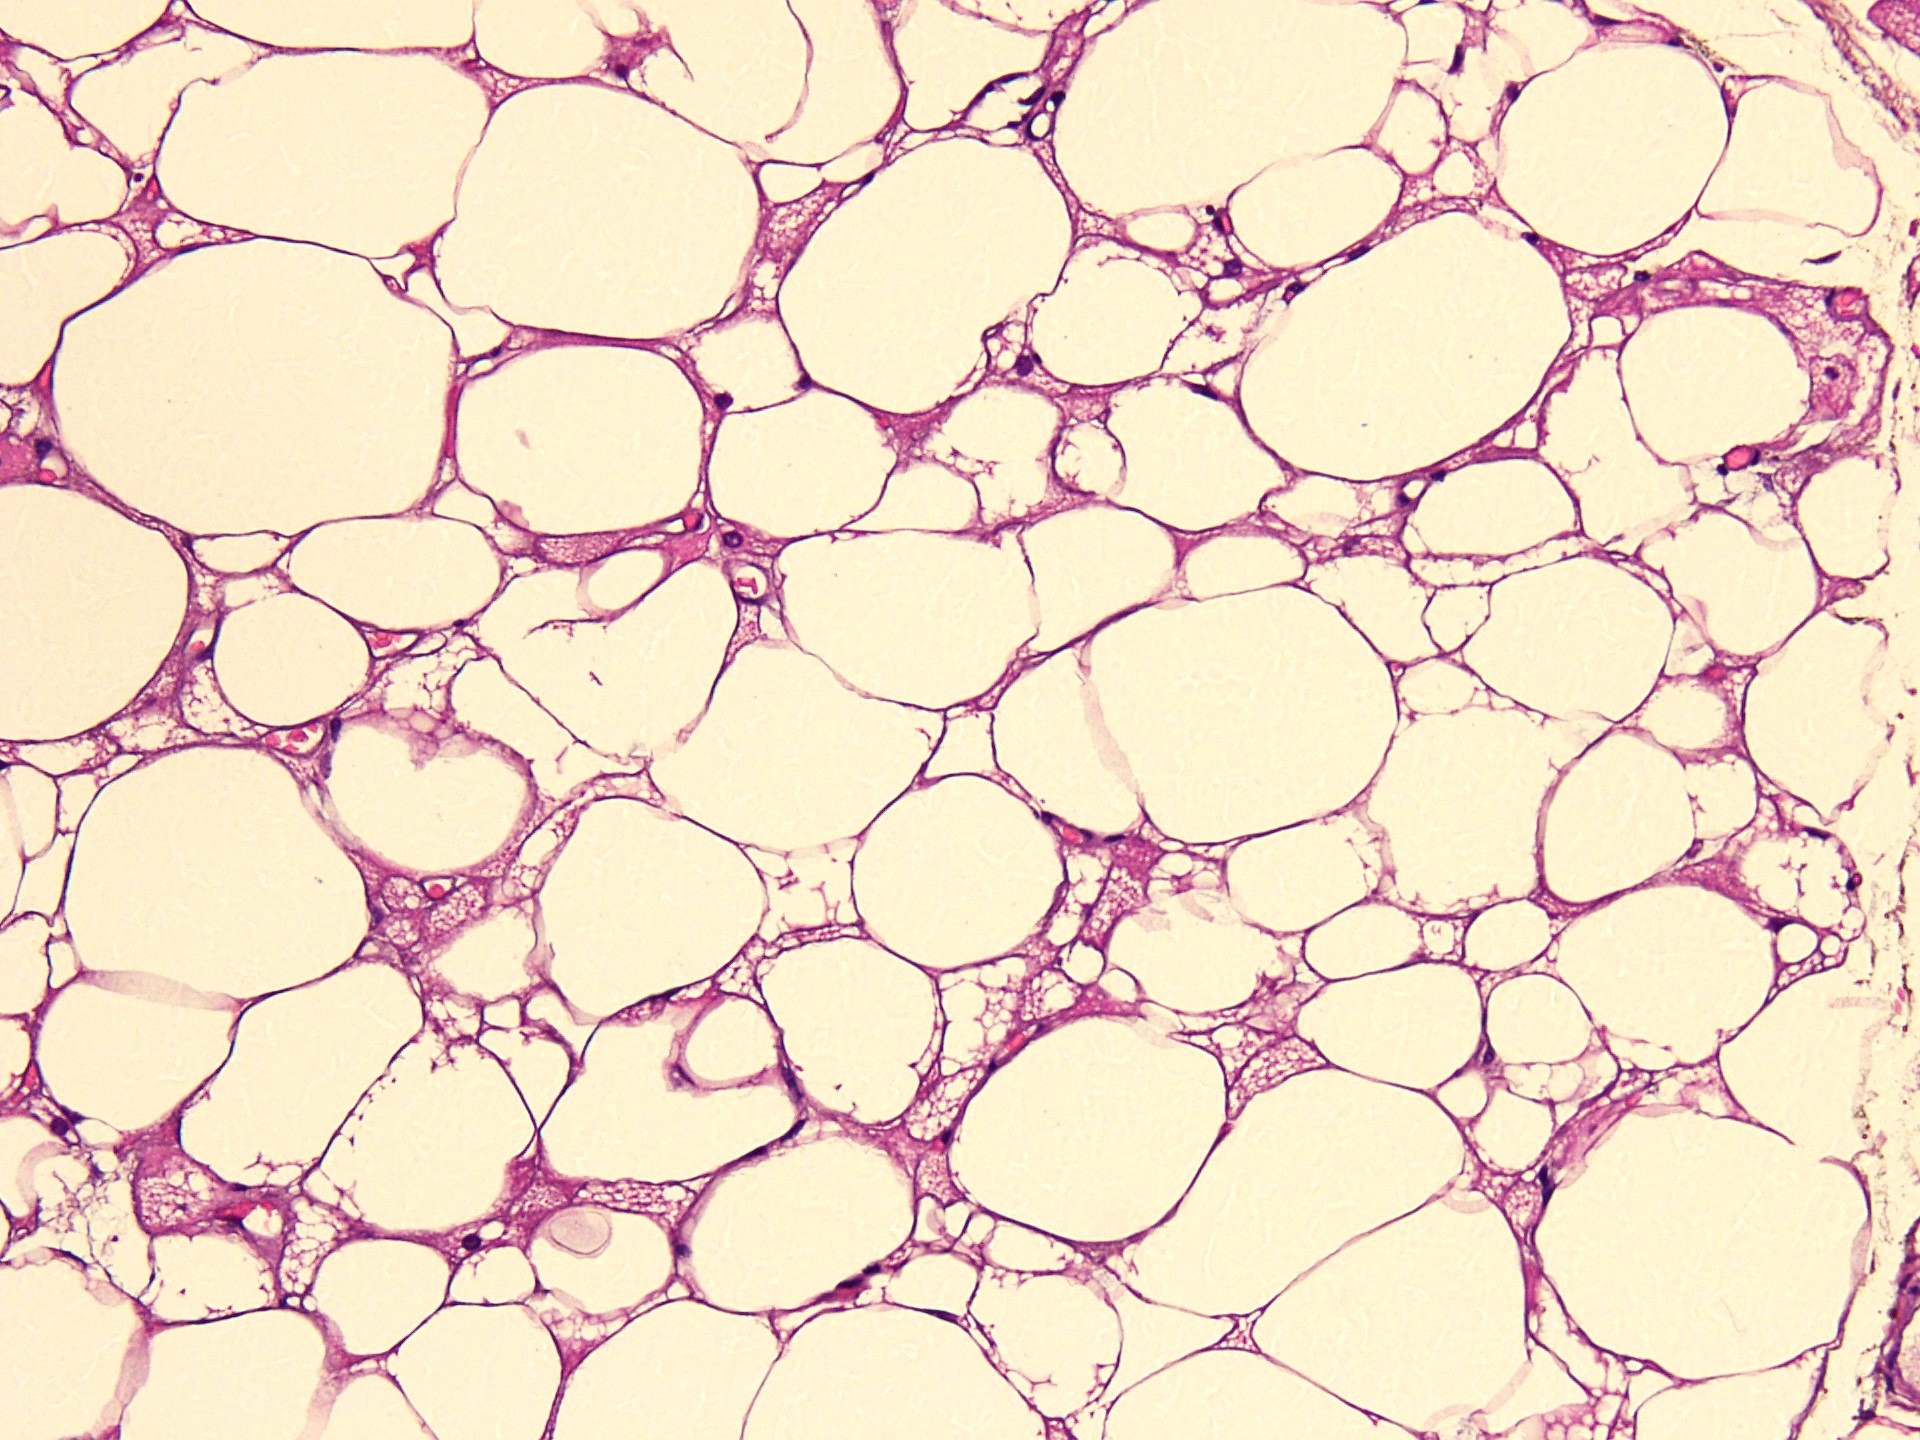

Microscopic (histologic) description

- Neoplastic lesion composed of polygonal brown fat cells with stromal cells in the background (Case Rep Oncol 2017;10:438)

- Large number of pale and eosinophilic brown fat cells with multivacuolated, eosinophilic granular cytoplasm and small central nucleus (about 70%) admixed with variable amount of univacuolated white cells (Case Rep Oncol 2017;10:438, Am J Case Rep 2020;21:e921447, J Comput Assist Tomogr 2019;43:793, J Pathol Transl Med 2017;51:499, Am J Surg Pathol 2018;42:951, Virchows Arch 2021;478:527)

- Multivacuolations resemble lipoblasts

- Morphological variations or subtypes: typical, myxoid (9%), lipoma-like (7%), spindle cell (2%), thick bundles of collagen fibers, presence of mast cells and exclusively containing brown fat cells (Case Rep Oncol 2017;10:438, Am J Case Rep 2020;21:e921447, Virchows Arch 2021;478:527)

- Cytological atypia, necrosis and mitosis is unusual (J Pathol Transl Med 2017;51:499, Am J Surg Pathol 2018;42:951, BMC Surg 2021;21:30)

Microscopic (histologic) images